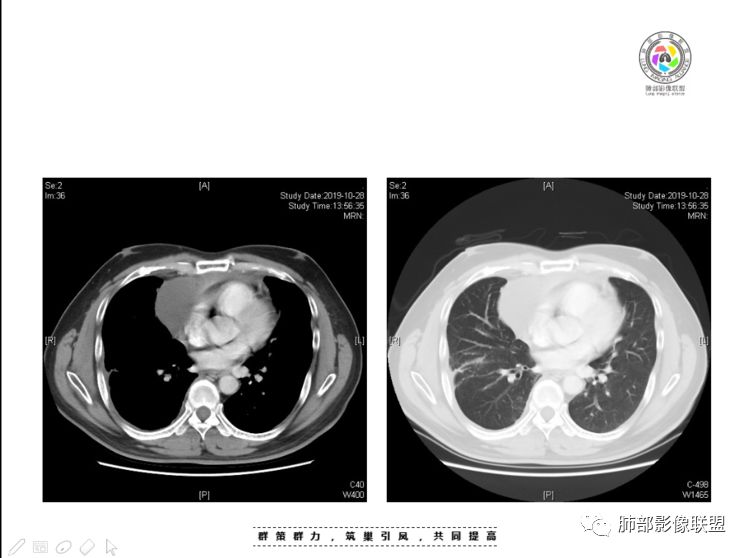

本例纵隔与肺内两处病变,回顾总结分析:

1、右肺内病灶,病灶呈结节样,边缘欠规则,局部膨隆,叶间裂胸膜牵拉凹陷,再看相应支气管腔堵塞截断,临床资料胸水中查到癌细胞,均提示病灶倾向恶性,腺癌的病理意见与之相吻合。

2、前纵隔内病灶囊实性混杂密度病灶,囊性病灶主要位于右侧,张力较高,有分隔影,囊壁右侧缘光整,病灶左侧实性部分边界不清明显强化,病灶肺瘤交界面大部分边界清楚,部分模糊。

前纵隔肿块伴囊变坏死常见以有胸腺瘤、胸腺癌、淋巴瘤和生殖细胞肿瘤。